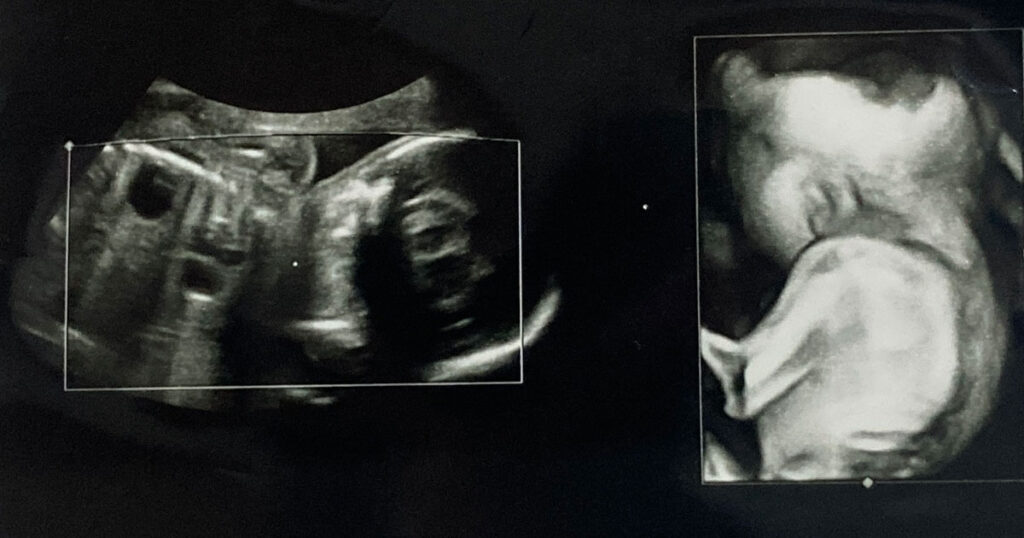

潜在二分脊椎症は、赤ちゃんが母親の子宮内で成長しているときに初めて発症します。この症状は脊椎に影響を及ぼし、正しく形成されません。隠れ二分脊椎症の人では、椎骨または脊椎の骨の一部が完全に閉じることができません。

研究者らは、なぜある人が隠れ二分脊椎症になるのか、他の人はそうではないのかについては確信を持っていない。しかし、母親が妊娠中に十分な葉酸を摂取していない赤ちゃんでは、脊髄欠損が発生する可能性が高くなります。